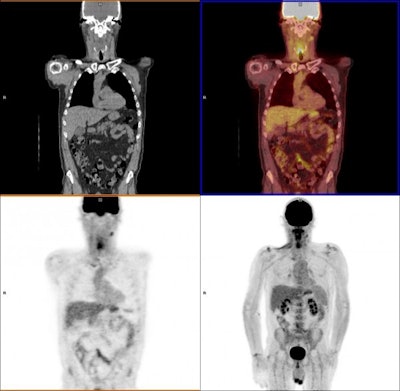

Using PET/CT scans to assess response to therapy can help patients with head and neck cancer avoid invasive post-treatment surgery to remove any remaining cancer cells, according to a U.K. study published online March 23 in the New England Journal of Medicine.

FDG-PET/CT is well-known for identifying both structural and metabolic abnormalities in tumors. One published meta-analysis reported that FDG-PET/CT achieved negative predictive values of 94% to 96% among head and neck squamous cell cancer patients after treatment.

Twelve weeks after their last cancer treatment, patients assigned to the planned neck dissection group were scanned using CT or MRI, while subjects in the experimental, surveillance group underwent PET/CT scans to assess the results of therapy.

Patients who had significant FDG uptake on PET/CT scans after 12 weeks of treatment were classified as having an incomplete nodal response, while mild or no FDG uptake in enlarged nodes or mild FDG uptake in normally sized nodes was considered an equivocal response. These patients subsequently underwent neck dissection. All other results were deemed complete responses to therapy.